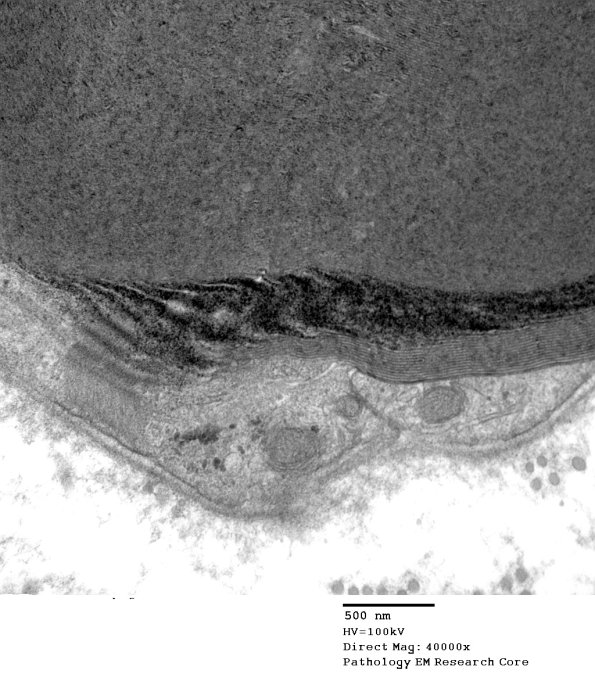

Washington University Experience | PERIPHERAL NEUROPATHY | 3 NORMAL MYELIN & SCHWANN CELLS | 3 Schmidt-Lanterman Clefts | 10A3 SLC (Case 10) EM 14M 149 - Copy

Higher magnification of image #10A2. (electron micrograph)